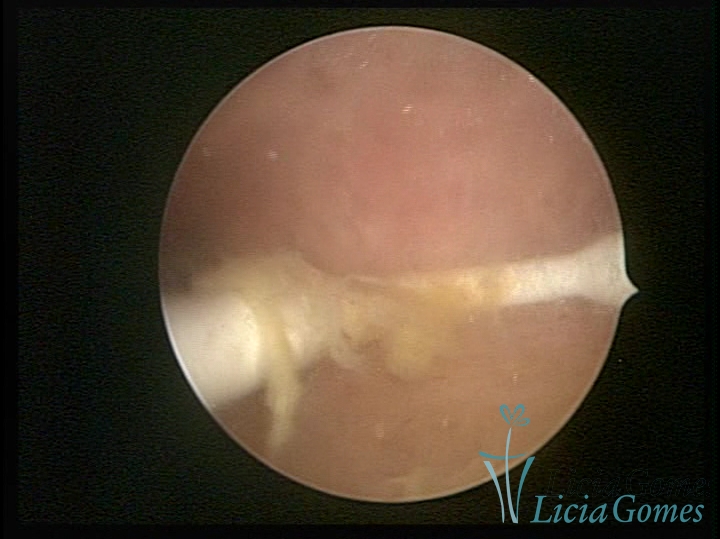

Myometrium punctured IUD

×